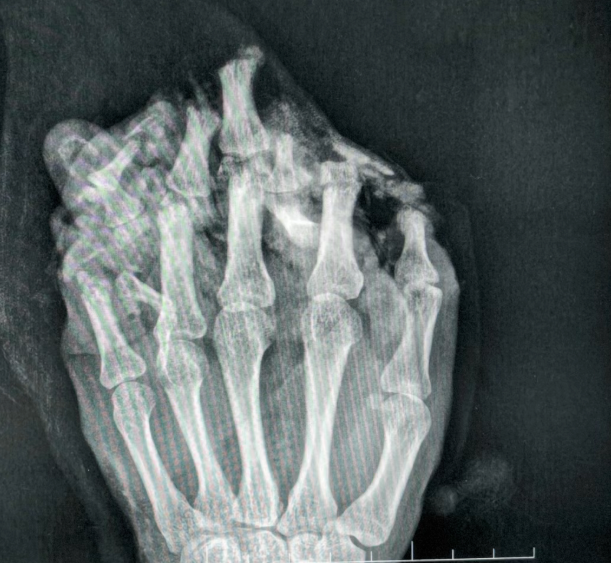

近日,一名男子在工作时

左手不慎被机器碾压

导致严重损毁

拍片显示左手伤情严重

医生及时进行手术

为覆盖巨大创面

将断手“种”在带有自身血供的腹部皮肤上

为后续所有修复提供了生存的土壤